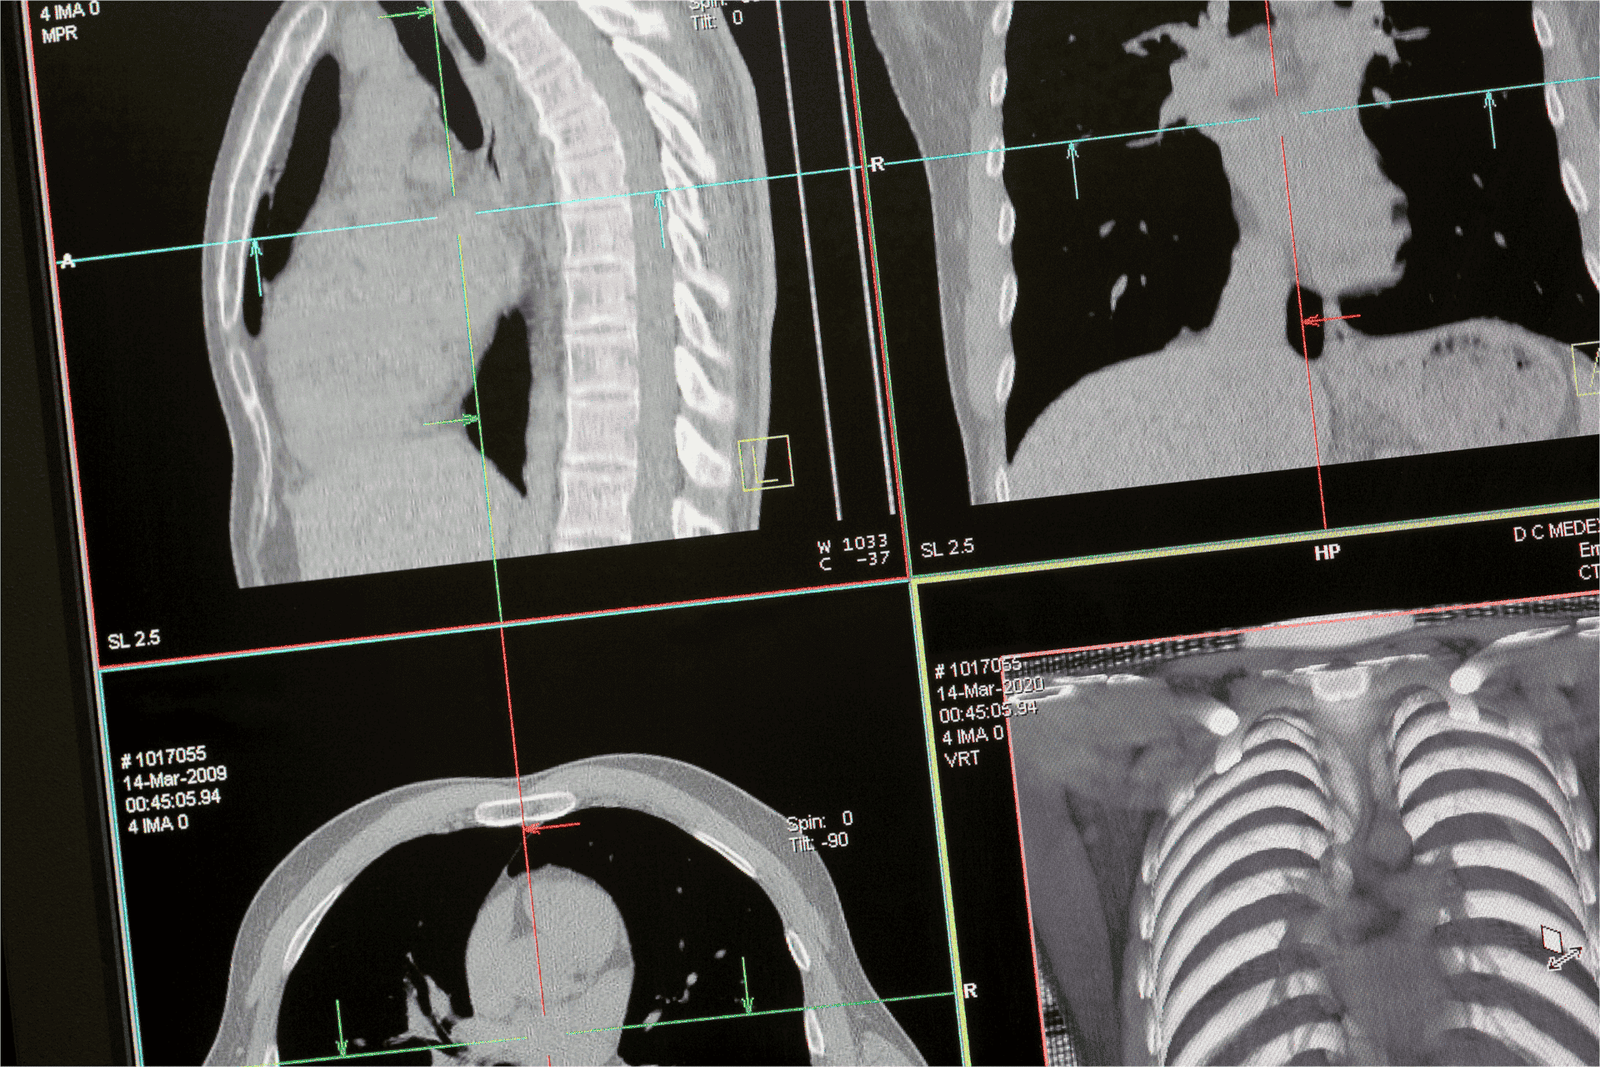

AI’s integration into diagnostic imaging extends beyond MRIs. As algorithms become more sophisticated, AI’s role in interpreting other medical images, such as CT scans and X-rays, is also expanding. This cross-modality capability further amplifies AI’s utility in diagnostic radiology, offering clinicians a unified platform for diverse image analysis.